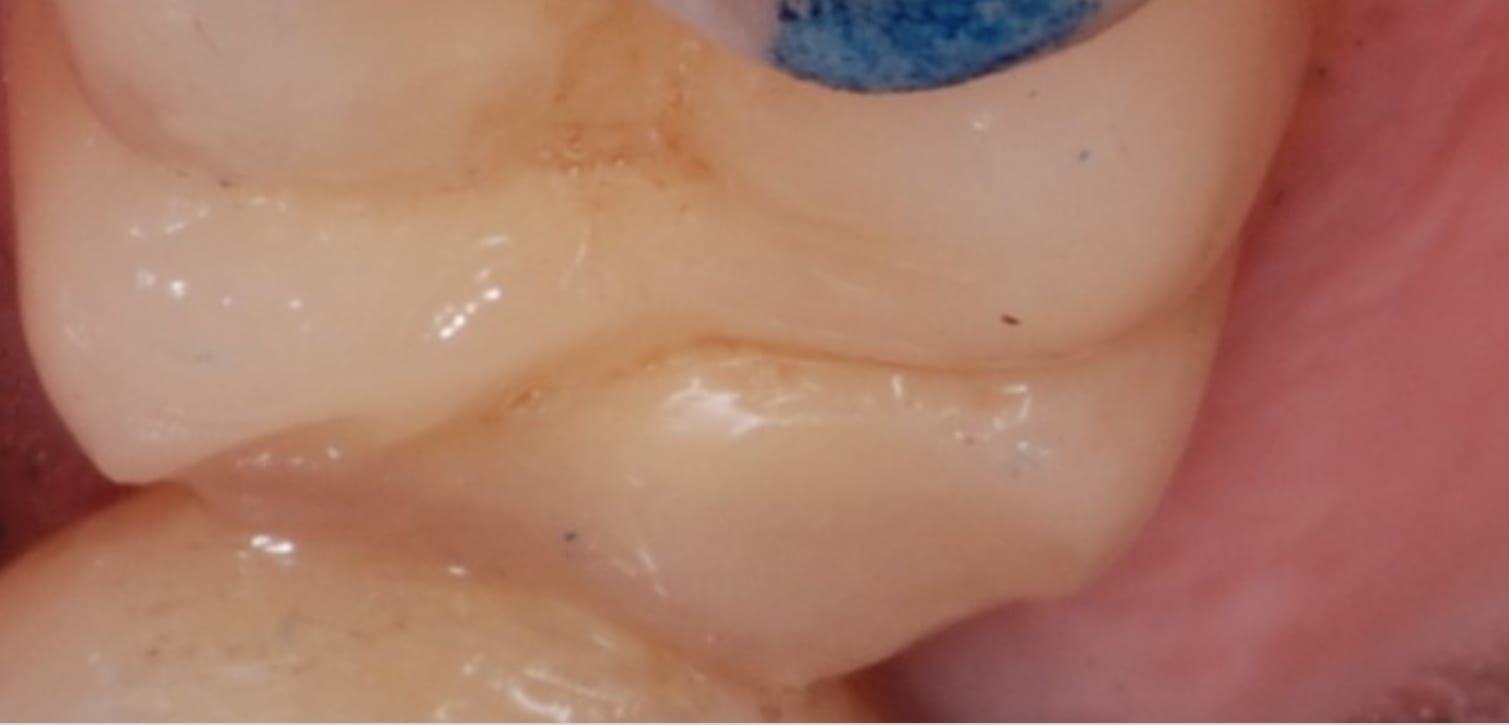

Oui point de contacts encore présents et bien serrés, le fil claque bien avec douleurs au passage du fil.

pourtant , sa couronne "fer" est toute mate en distal , pourquoi ? on dirait qu il y a ou qu il y a eu frottement mais pas avec un truc dur . .

et sa ceram , elle est cassée en distal ?